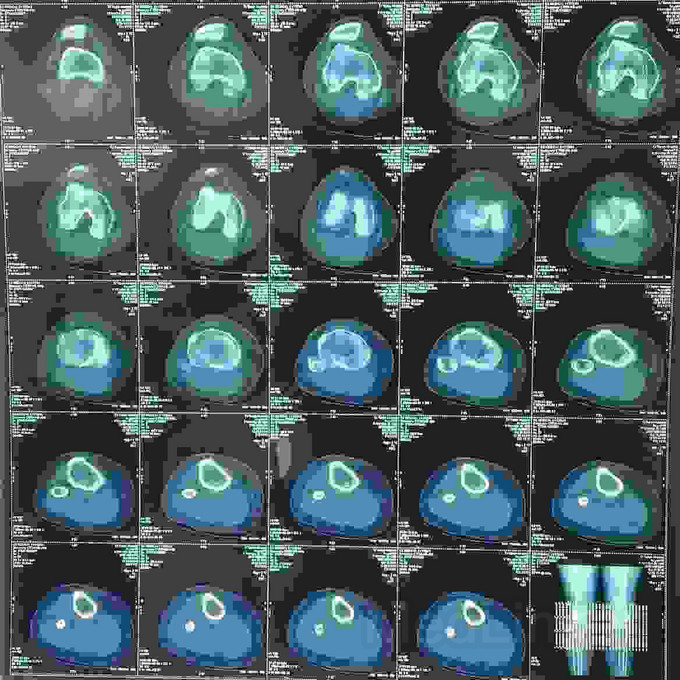

患者女,19岁,双膝关节习惯性髌骨脱位10余年,多家医院建议手术治疗,2个月前摔伤致左髌骨脱位,于某院行手术治疗,经家人商讨后决定再行右膝手术治疗来我院。请老师们指点是否需要调整髌骨远端力线?做何手术最为简单有效?具体是做单纯外侧支持带松解?外侧支持带松解+内侧关节囊缩紧筋膜成形?外侧支持带松解+髌腱手术?外侧支持带松解+胫骨结节内移?还是外侧松解+内侧紧缩成形+胫骨结节内移?还是什么?